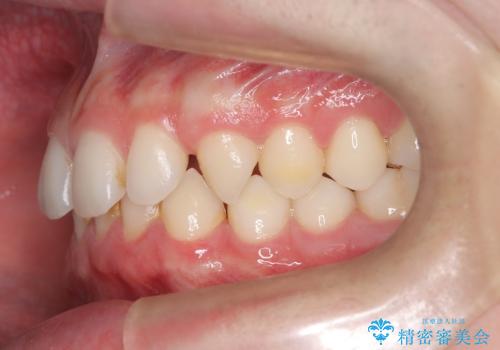

- 主訴:上の歯列の空隙を閉じたい

上顎前歯部に空隙が目立ちました。ワイヤー矯正、インビザライン(マウスピース矯正)どちらの方法でも適用症例と説明し、ワイヤー矯正治療(審美装置)を希望されました。

上顎歯列の空隙を閉じるのと一緒に、ディープバイト気味の被蓋も下顎前歯の圧下を行い改善しました。

矯正治療期間:2年ちょうど